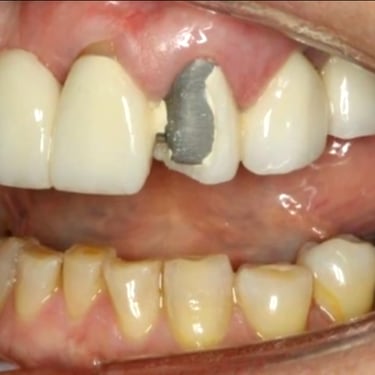

Fractura de la prótesis sobre implante

La fractura de la prótesis sobre implante es una ruptura o daño en la corona, puente o dentadura soportada por implantes.

Los pacientes pueden notar una prótesis suelta o dañada.

El tratamiento incluye la reparación o reemplazo de la prótesis afectada